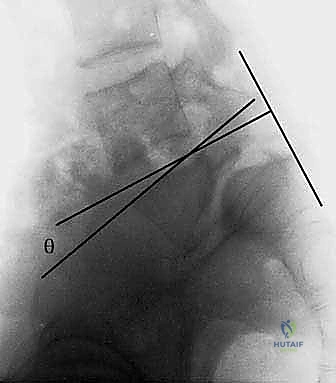

نظام تصنيف مايردينغ (Meyerding Classification)

لتقييم مدى خطورة الانزلاق الفقاري وتحديد خطة العلاج المناسبة، يستخدم الأطباء، وعلى رأسهم الأستاذ الدكتور محمد هطيف، نظام تصنيف يُعرف باسم "تصنيف مايردينغ". يقيس هذا النظام نسبة انزلاق الفقرة العلوية بالنسبة للفقرة السفلية:

- الدرجة الأولى (Grade I): انزلاق بنسبة 0% إلى 25%. (غالباً ما تُعالج تحفظياً).

- الدرجة الثانية (Grade II): انزلاق بنسبة 26% إلى 50%.

- الدرجة الثالثة (Grade III): انزلاق بنسبة 51% إلى 75%. (غالباً ما تتطلب تدخلاً جراحياً).

- الدرجة الرابعة (Grade IV): انزلاق بنسبة 76% إلى 100%.

- الدرجة الخامسة (Grade V أو Spondyloptosis): انزلاق كامل للفقرة لتسقط تماماً أمام الفقرة التي تحتها، وهي حالة شديدة التعقيد تتطلب مهارة جراحية فائقة.

هي الخطوة الأولى والأساسية. يتم التقاط صور للعمود الفقري من عدة زوايا (أمامية، جانبية، ومائلة). الأشعة الجانبية هي الأهم لتحديد درجة الانزلاق (حسب تصنيف مايردينغ). كما يتم إجراء أشعة ديناميكية (أثناء الانحناء للأمام وللخلف) لتقييم مدى "عدم الاستقرار" (Instability) وحركة الفقرة أثناء الحركة. -